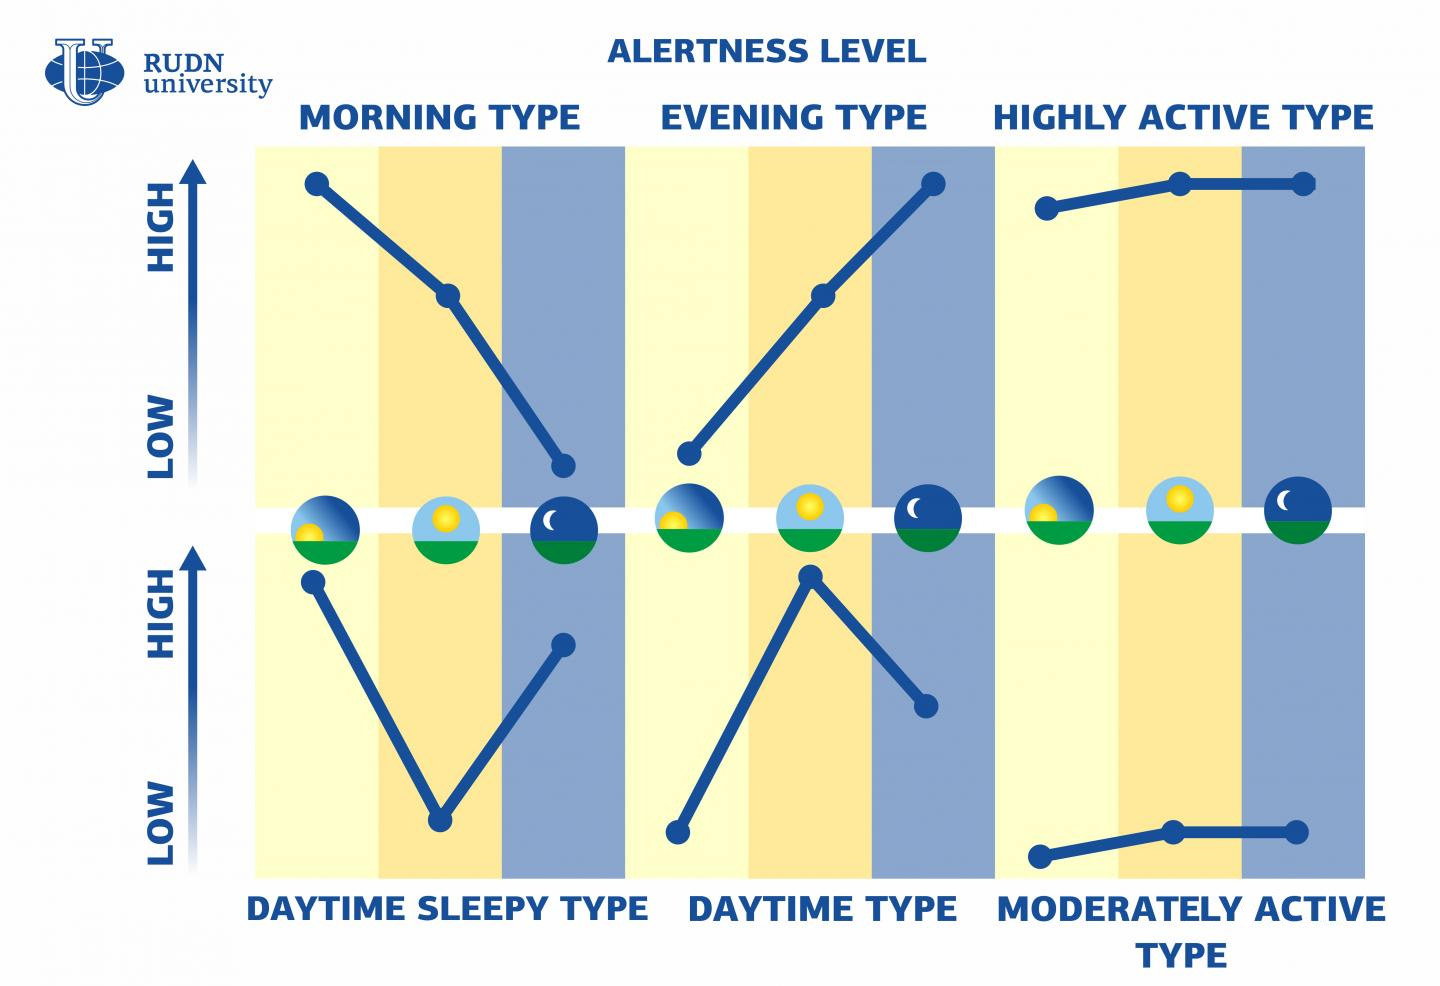

Each individual’s circadian rhythm exhibits unique variations. Kianersi pointed out that previous research had implied a correlation between a nocturnal disposition and an increased prevalence of health complications, alongside risk factors such as elevated rates of tobacco consumption and reduced levels of physical activity, when compared to individuals with more conventional sleep-wake patterns.

Approximately 8 percent of these individuals characterized themselves as night owls, demonstrating greater physical and mental vigor in the late afternoon or evening, and remaining active well past customary bedtime.

Conversely, approximately a quarter identified as early birds, exhibiting peak productivity during daylight hours and retiring early. The remaining participants fell into the average category, occupying an intermediate position.